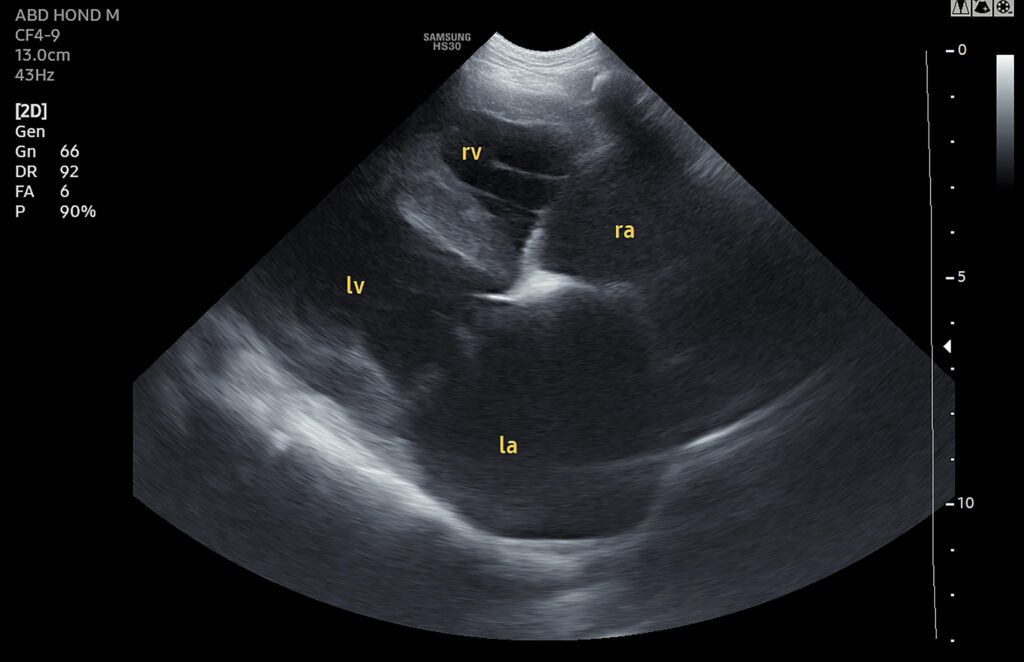

Met een hartecho kunnen we alle onderdelen van het hart goed zien, opmeten en de verhoudingen bepalen. Op deze manier kunnen we uitzoeken wat er precies mis is met het hart en hoe we het dier, waar mogelijk, kunnen helpen om het hart zo lang mogelijk zo goed mogelijk te laten werken. Dit is belangrijk, want net als bij mensen kan een hartprobleem bij dieren grote gevolgen hebben. Denk maar aan vocht achter de longen en vocht in de buik, maar er kan ook sprake zijn van problemen met de bloeddruk, de nieren of de schildklier.

De dieren liggen tijdens het onderzoek rustig op hun zij op een lekker dik kussen en laten het onderzoek vaak goed toe. Er wordt een klein stukje vacht geschoren ter hoogte van de rechter oksel zodat we het hart goed in beeld kunnen brengen.

We spreken samen met u een tijd af waarop u uw huisdier weer op kunt halen. Op dat moment staat de dierenarts u zelf te woord en bekijkt u samen de echobeelden. Op deze manier proberen we zo goed mogelijk weer te geven wat er aan de hand is met het hart en kunt u meteen samen met de dierenarts het behandelplan bespreken. Wat dit plan is, wisselt per patiënt en is dus niet van tevoren in te schatten. Wel willen we bij patiënten met een bewezen hartprobleem bij voorkeur, afhankelijk van het probleem, de echo (half)jaarlijks herhalen om veranderingen zo snel mogelijk te kunnen vinden.